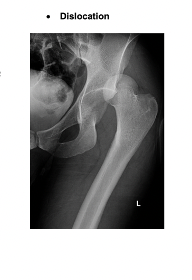

Which direction of hip dislocation is the most common and why?

Posterior because anterior ligaments are stronger

Which structure at risk following hip dislocation

Nerve injury – sciatic nerve is most commonly affected

In what position is affected limb likely to be in posteiror hip dislocation

Flexion, adduction and internal rotation with shortening of the leg.

2 Types dislocaiton of the hips